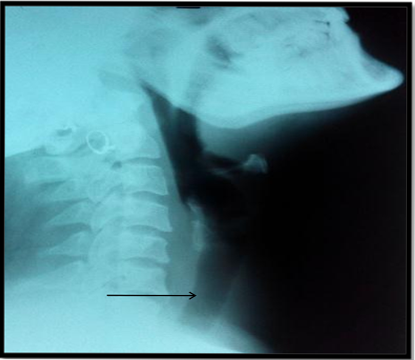

Imaging in form of radiographs of the neck and chest revealed a soft tissue density lesion in the superior mediastinum with well-defined lateral margins; however the inferior margin was not well defined. The trachea was central with no evidence of any compression (Figure 2A & 2B).

Figure 2A Soft tissue swelling (likely thyroid gland) in anterior aspect of lower cervical region with no trachea compression (arrow).